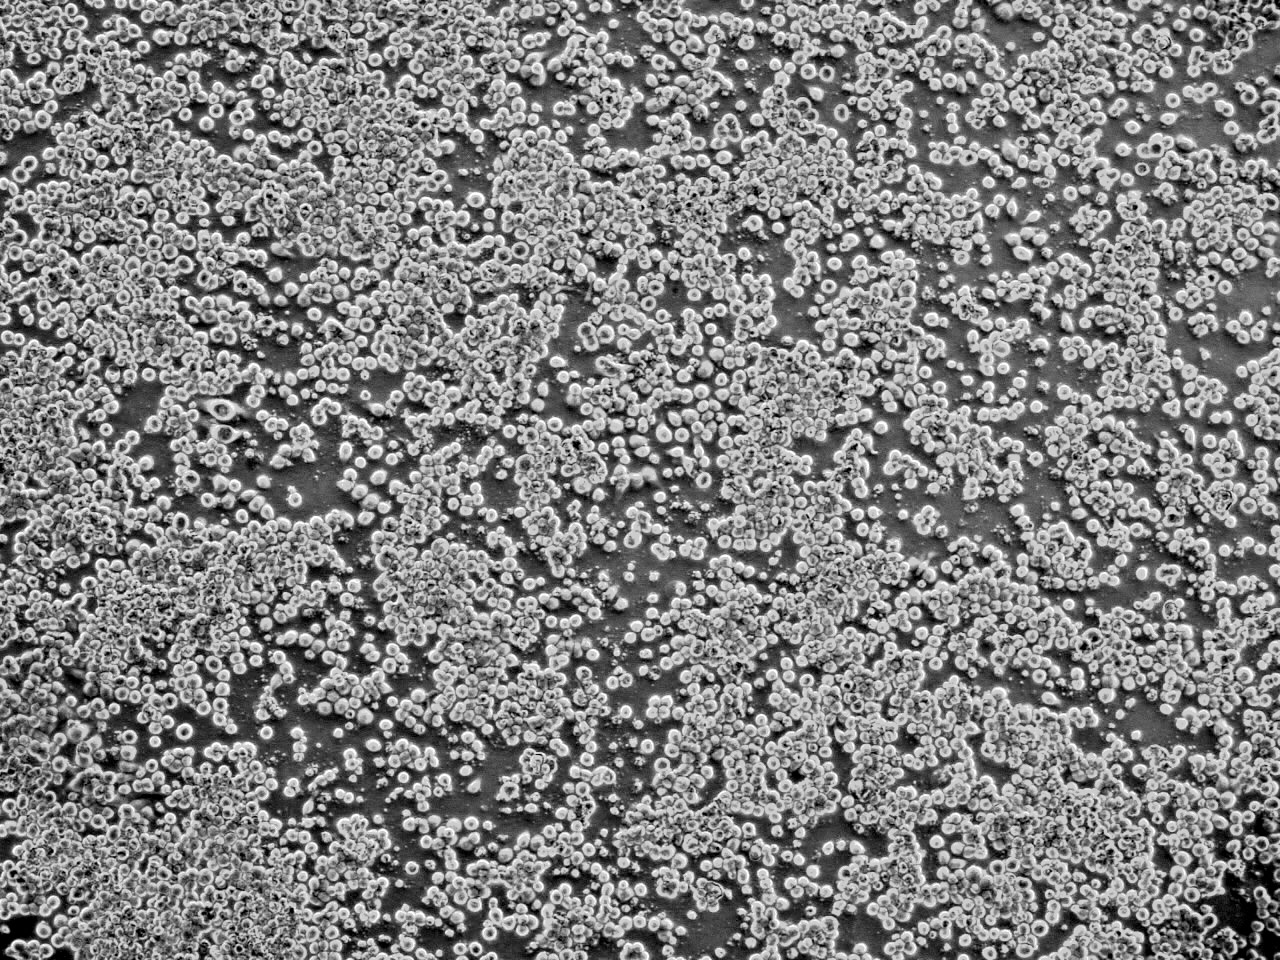

用 以 製 造 戊 型 肝 炎 疫 苗 的 昆 蟲 細 胞

香 港 科 技 大 學 ( 科 大 ) 與 北 京 綠 竹 生 物 製 藥 有 限 公 司 合 作 研 發 戊 型 肝 炎 疫 苗 , 首 次 利 用 獨 特 的 昆 蟲 細 胞 系 統 和 方 法 來 生 產 免 疫 原 蛋 白 , 為 影 響 全 球 三 分 一 人 口 的 傳 染 病 尋 求 預 防 方 法 。 這 項 世 界 首 創 的 疫 苗 技 術 由 科 大 生 命 科 學 部 謝 雍 教 授 帶 領 團 隊 研 發 , 能 簡 化 生 產 程 序 及 降 低 生 產 成 本 。

戊 型 肝 炎 病 毒 ( HEV ) 感 染 是 一 個 重 要 的 公 共 衞 生 問 題 , 在 世 界 許 多 地 區 造 成 急 性 肝 炎 的 大 爆 發 。 研 發 出 有 效 預 防 戊 型 肝 炎 的 疫 苗 迫 在 眉 睫 , 北 京 綠 竹 生 物 製 藥 有 限 公 司 於 2010 年 5 月 和 香 港 科 技 大 學 研 究 開 發 公 司 簽 訂 了 合 作 開 發 研 製 戊 型 肝 炎 疫 苗 的 協 議 , 2010 年 9 月 啟 動 該 項 目 , 經 過 一 年 半 的 努 力 , 科 大 謝 雍 教 授 帶 領 的 團 隊 終 於 建 立 了 用 昆 蟲 細 胞 表 達 戊 型 肝 炎 病 毒 疫 苗 的 創 新 系 統 , 臨 床 前 研 究 工 作 正 在 按 計 劃 進 行 , 目 前 進 展 順 利 。 科 大 和 綠 竹 建 立 的 獨 特 表 達 系 統 和 方 法 , 能 夠 直 接 和 高 效 地 表 達 病 毒 抗 原 , 這 在 世 界 上 屬 首 創 , 並 且 由 於 產 生 的 抗 原 容 易 回 收 , 大 大 簡 化 生 產 程 序 , 降 低 生 產 成 本 , 得 到 更 能 被 廣 大 群 眾 所 接 受 的 產 品 。 它 的 特 點 是 用 昆 蟲 細 胞 能 夠 表 達 比 較 長 的 蛋 白 片 段 , 使 其 包 括 更 多 的 抗 原 決 定 簇 , 尤 其 是 T 細 胞 的 抗 原 決 定 簇 ; 昆 蟲 細 胞 表 達 的 蛋 白 折 疊 方 式 更 接 近 於 天 然 蛋 白 , 這 些 優 點 都 表 明 其 表 達 的 蛋 白 免 疫 原 性 較 強 。